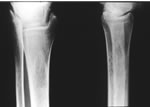

Ревматоидный артрит – хроническое системное заболевание соединительной ткани с прогрессирующим симметричным эрозивно-деструктивным поражением преимущественно периферических суставов.

Ревматоидный артрит – наиболее распространенное хроническое воспалительное заболевание суставов, характеризующееся формированием опухолеподобной гиперплазии синовиальной оболочки.